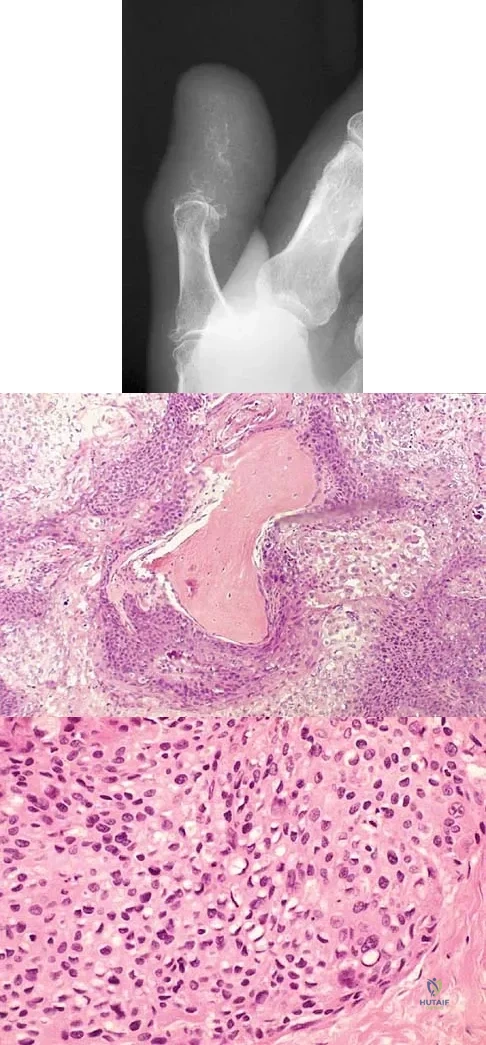

A 69-year-old man has a painful slow-growing lesion of the distal phalanx of his thumb. History reveals that he has had chronic osteomyelitis of the thumb for the past 12 years. The radiograph and biopsy specimens are seen in Figures 9a through 9c. Treatment should consist of